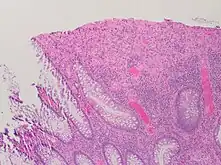

| A micrograph demonstrating cryptitis, a microscopic correlate of colitis. H&E stain. | |

An important investigation in the assessment of colitis is biopsy for histopathology. A very small piece of tissue (usually about 2mm) is removed from the bowel mucosa during endoscopy and examined under the microscope by a histopathologist. A biopsy report generally does not state the diagnosis, but should state any presence of chronic colitis, give an indication of disease activity, as well as state the presence of any epithelial damage (erosions and ulcerations).[4]

Histopathology findings generally associated with chronic colitis include:[4]

Other findings include basal plasmacytosis and mucin depletion.[4] Histopathology findings generally associated with active colitis include:[4]

Gland destruction

Ulceration (seen here as absence of epithelium, and granulation tissue with many fibroblasts)